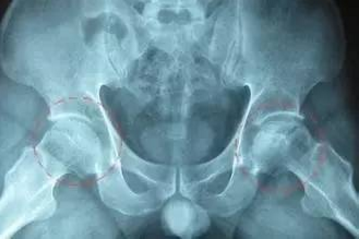

股骨头坏死即股骨头无菌性坏死,或股骨头缺血性坏死,是由于多种原因导致的股骨头局部血运不良,从而引起骨细胞进一步缺血、坏死、骨小梁断裂、股骨头塌陷的一种病变。该病主要表现为髋关节或其周围关节疼痛,进一步发展可导致髋关节的功能障碍,严重影响患者的生活质量和劳动能力,若不及时就医,还可导致终身残疾。在临床中,以局部创伤、应用激素药物、过量饮酒引起的股骨头坏死最为多见。其共同的核心问题是各种原因引起的股骨头的血液循环障碍,而导致骨细胞缺血、变性、坏死。

1、血供少。股骨头的血供主要依靠囊外动脉环发出的外侧支持带和内侧支持带动脉,血管少且薄弱,当一支血管被阻断而另一支不能及时代偿时,即会造成股骨头的供血障碍,血供少是股骨头坏死的病因最终表现,任何病因都要经过这步,才能导致股骨头坏死。

2、剪力大。髋关节不同于其它负重关节那样两骨端关节力线垂直,股骨干与股骨头颈之间形成132度的角,躯干的重力是由髋臼通过股骨头,颈移行至股骨干,力线不垂直,就形成了剪力。因此,其头颈所承受的生理压力要比其它关节大得多。

4、负重大。髋关节是人体负重最大的关节,支撑着整个躯干的重量,如果身体负重,头与臼之间压力必然增大,长期保持着这种较大的压力,不但容易造成结构上的损伤,而且影响局部的血液循环,从而引发缺血性坏死。